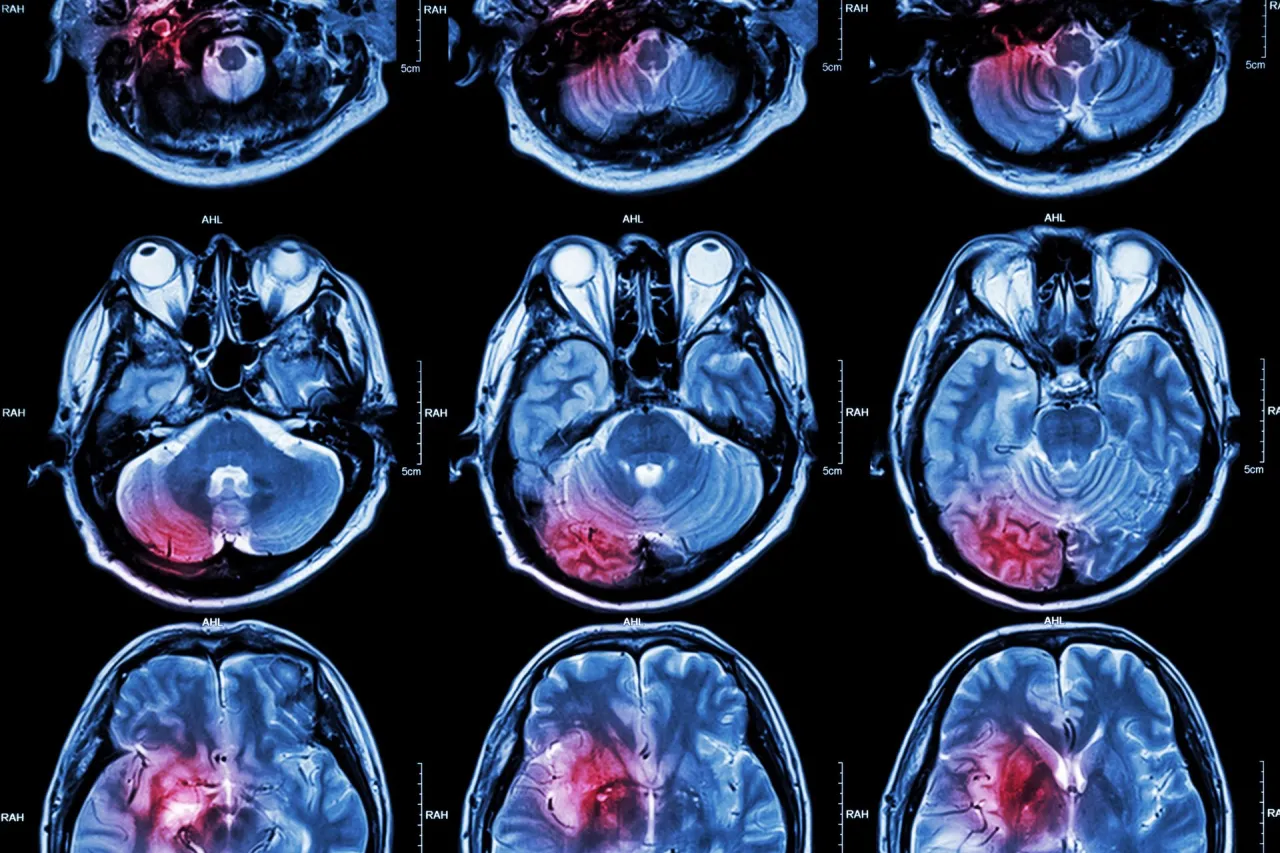

Udar mózgu to nagłe zaburzenie krążenia krwi w mózgu, które prowadzi do obumierania jego komórek. To stan niezwykle poważny, wymagający natychmiastowej interwencji medycznej. Jako Szymon Dudek, wielokrotnie widziałem, jak kluczowe jest zrozumienie, że udar nie jest jednorodną chorobą. W rzeczywistości ma on dwa główne oblicza, a ich rozróżnienie jest fundamentalne, ponieważ przyczyny i mechanizmy ich powstawania są zupełnie inne. W Polsce udar dotyka od 60 do nawet 90 tysięcy osób rocznie, co czyni go drugą najczęstszą przyczyną zgonów i głównym powodem niepełnosprawności wśród dorosłych. Te statystyki jasno pokazują, jak ważne jest, aby każdy z nas miał świadomość zagrożenia i wiedział, co może do niego prowadzić.

Udar niedokrwienny, często nazywany zawałem mózgu, stanowi zdecydowaną większość, bo aż 80-87% wszystkich przypadków udarów. Powstaje on, gdy tętnica doprowadzająca krew do mózgu zostaje zablokowana, co skutkuje niedotlenieniem i obumieraniem komórek nerwowych. Najczęstszymi przyczynami są tu miażdżyca oraz zator. Miażdżyca to proces, w którym w ścianach tętnic odkładają się blaszki cholesterolowe. Z czasem blaszki te zwężają światło naczynia, a na ich powierzchni mogą tworzyć się zakrzepy, które całkowicie zamykają tętnicę. Drugą istotną przyczyną jest zator w tym przypadku skrzeplina, często powstała w sercu (na przykład w wyniku migotania przedsionków), odrywa się i z prądem krwi przemieszcza się do tętnicy mózgowej, blokując ją. To jak nagłe zatkanie rury w systemie hydraulicznym przepływ ustaje, a obszar za zatorowaniem cierpi.

Udar krwotoczny, znany również jako wylew, jest mniej powszechny, ale często bardziej dramatyczny w przebiegu. W tym przypadku dochodzi do pęknięcia ściany naczynia krwionośnego w mózgu, co prowadzi do wylewu krwi do tkanki mózgowej. Krew ta, gromadząc się, uciska na struktury mózgu i uszkadza je. Główną i najczęstszą przyczyną udarów krwotocznych jest niekontrolowane, długotrwałe nadciśnienie tętnicze. Wysokie ciśnienie krwi osłabia ściany tętnic, czyniąc je bardziej podatnymi na pęknięcia. Inne możliwe przyczyny to pęknięcie wrodzonych tętniaków (czyli uwypukleń ściany naczynia) lub malformacji naczyniowych, które są nieprawidłowymi połączeniami naczyń krwionośnych.Główne choroby prowadzące do udaru poznaj cichych sprawców katastrofy